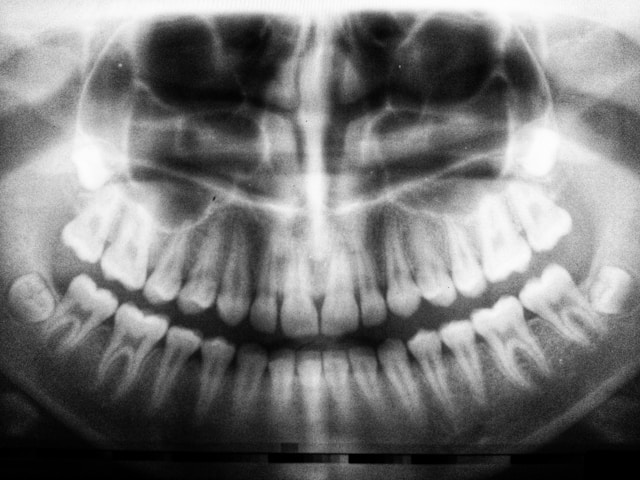

A prática da exodontia baseia-se em princípios mecânicos e requer uma avaliação pré-operatória cuidadosa, que inclui a análise da saúde geral do paciente e a condição do dente. Indicada principalmente para dentes afetados por cáries extensas, abscessos ou cistos, a exodontia pode ser necessária em casos de infecção ou trauma.

Os procedimentos de exodontia incluem técnicas como a extração fechada ou aberta, dependendo da situação clínica. Uma extração fechada pode ser realizada com o uso de elevadores e fórceps, minimizando a necessidade de intervenção invasiva. Nessa técnica, o dente é mobilizado através de movimentos suaves para evitar fraturas.

Por outro lado, uma extração aberta pode ser necessária se o dente estiver submerso ou quebrado, exigindo uma incisão e, por vezes, a remoção de tecido ósseo. A utilização de produtos anestésicos é vital para manter o conforto do paciente durante todo o processo, permitindo uma extração segura e com menor desconforto possível.